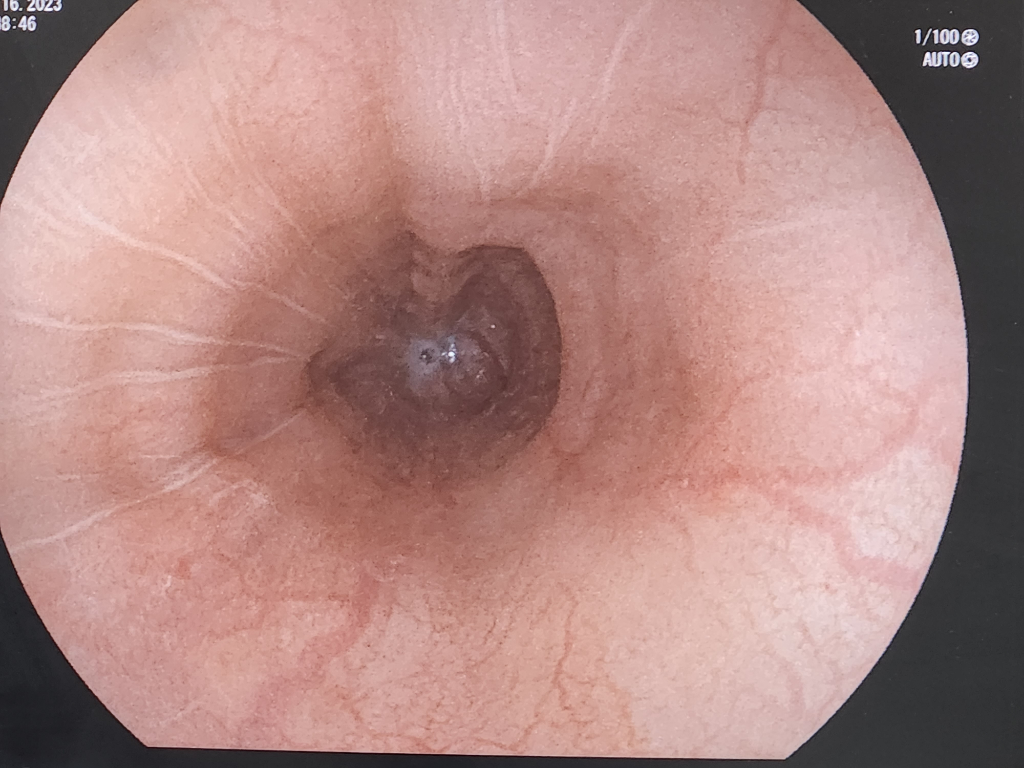

소화가 너무 안되서 위내시경을 받았는데 궤양? 같은게 나왔습니다. 모양이 안좋은 편인가요? 혹시 암일수도 있나요? 위상태는 어떤편인가요 ㅠㅠ 정확하지 않아도 됩니다. 알려주세요 부탁드립니다.

• 1번 째 사진